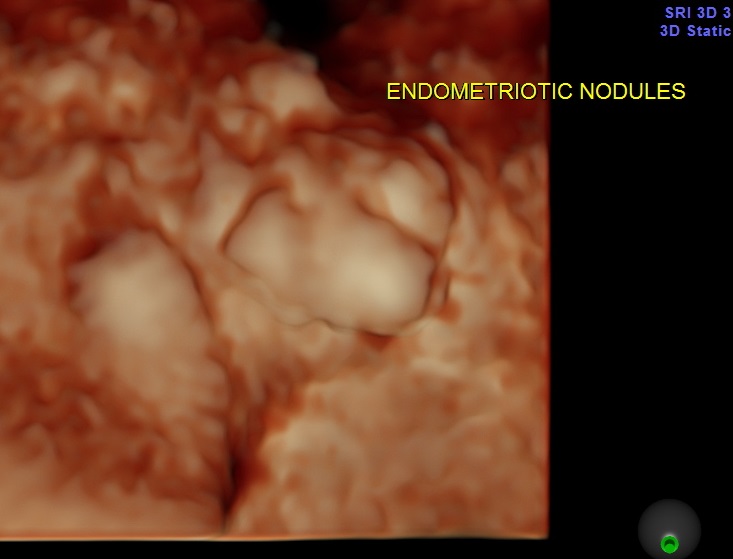

On evaluation she had a nodular swelling between the bladder and uterus. She had a few uro gynaecological consultations and cystoscopy and biopsy revealed endometriotic nodule. As she was reluctant to have any surgical correction , she was on conservative medical treatment . She also took hormonal treatment for endometriosis. The intensity of her symptoms reduced . She had come for her annual follow up scan and the pictures are given above.

The 3 D and 4D Live pictures of the endometriotic nodules are given above. The uro gynaecologist reviewed her and advised her to continue the conservative management.